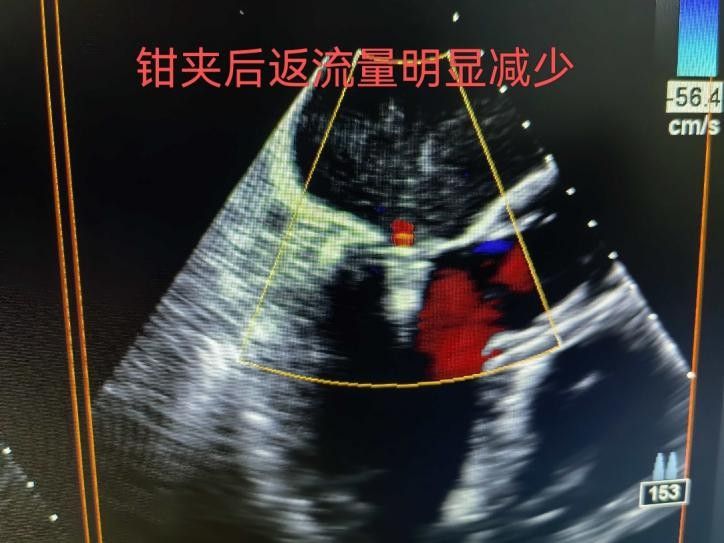

手術(shù)于11月4日下午進(jìn)行,通過股靜脈穿刺送入夾合器,在食道超聲實(shí)時(shí)引導(dǎo)下,精準(zhǔn)植入2枚瓣膜夾修復(fù)二尖瓣。整個(gè)過程歷時(shí)約2小時(shí),術(shù)中出血量僅50ml。術(shù)后次日,患者即可下床活動(dòng),復(fù)查顯示EF提升至46%,二尖瓣返流面積縮小至3.0cm2,左心房縮小至66mm,胸悶、氣短癥狀明顯緩解。